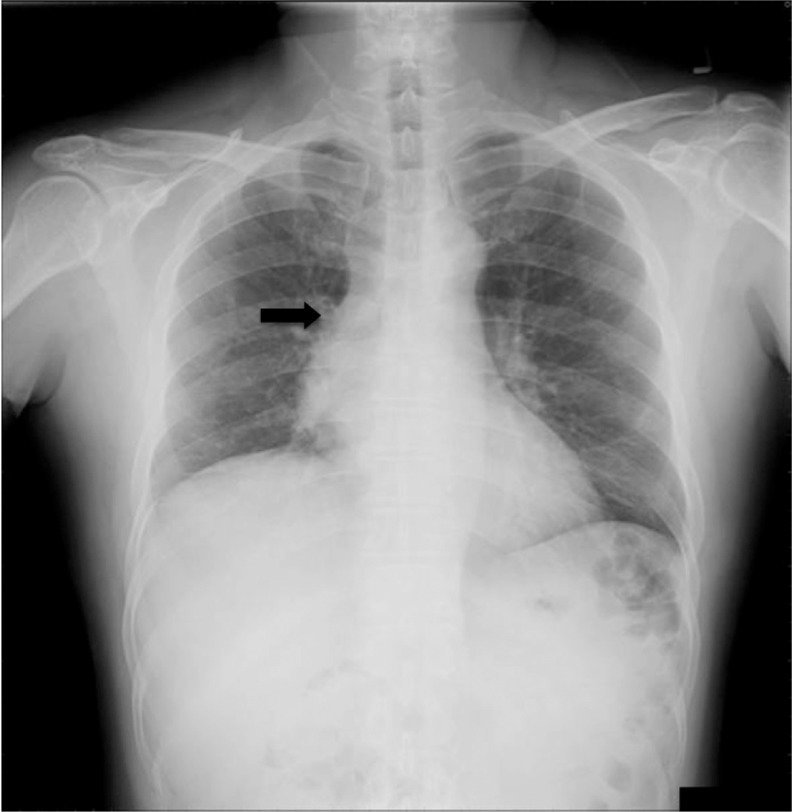

What does increased + absent lung markings indicate?

Increased = pathology (malignancy/ consolidation)

Absent = pneumothorax